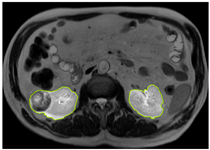

3.2.1. ROI Dataset

The images used in the study include different anatomical areas, such as the liver, spleen, and intestine. However, in order to process the data more quickly and provide more accurate results from the analysis, only the kidney areas (Regions of Interest, ROI) were extracted and evaluated. The Roboflow platform was used for spatial matching and segmentation of the kidneys. Polygonal ROI regions were defined by applying the semantic segmentation method, and then the transformations performed were verified by the radiologist, increasing the reliability of the system. In our study, MRI phase images were acquired at a resolution of 512 × 512 and the renal region of interest (ROI) was segmented and resized to 224 × 224 for input into the DenseNet architecture. In a similar study, Alhussaini et al. utilized 512 × 512 CT images and processed tumor-containing ROIs for their analysis; however, segmented region details were not provided [23]. Another study aimed to differentiate ccRCC from oncocytoma by extracting ROIs from T2-weighted images (T2-WI), pre-contrast T1-weighted images (T1-WI), and post-contrast arterial and venous phases. Tumor regions segmented at 100 × 100 mm were subsequently resized for input into the AlexNet model [24]. Unlike these studies, our approach involves segmenting the entire kidney, rather than solely the tumor region, to enable the deep learning model to leverage structural information for the organ as a whole.

Table 2 shows sample images containing ROI areas for different phases.

Table 2.

ROI areas in different phases.